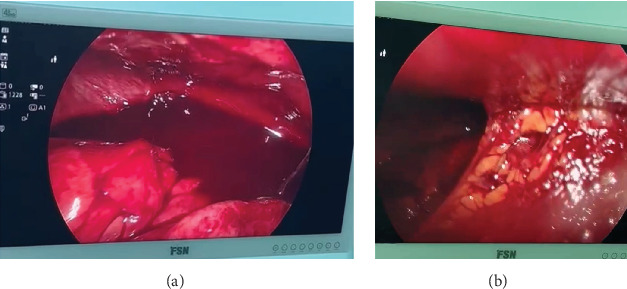

残端阑尾炎是阑尾切除术后罕见但严重的并发症,是由于阑尾切除不全而引起的。它通常与急性阑尾炎相似,但有非特异性症状,如腹痛、恶心、呕吐和发烧,使诊断具有挑战性。在这里,我们报告一个17岁的男性病例,他在接受开放性阑尾切除术后仅11天就出现了弥漫性腹痛,发烧和恶心。体格检查显示手术部位有压痛,影像学显示右下腹部有炎性改变。探查手术证实残端阑尾炎是由于保留阑尾组织,并切除。病人平静地康复了。

Stump appendicitis is a rare but serious complication following an appendectomy, resulting from incomplete removal of the appendix. It often mimics acute appendicitis with nonspecific symptoms, such as abdominal pain, nausea, vomiting, and fever, making diagnosis challenging. Here, we report the case of a 17-year-old male who presented with diffuse abdominal pain, fever, and nausea just 11 days after undergoing an open appendectomy. Physical examination revealed tenderness at the surgical site, and imaging showed inflammatory changes in the right lower quadrant. Exploratory surgery confirmed stump appendicitis due to retained appendiceal tissue, which was resected. The patient recovered uneventfully.